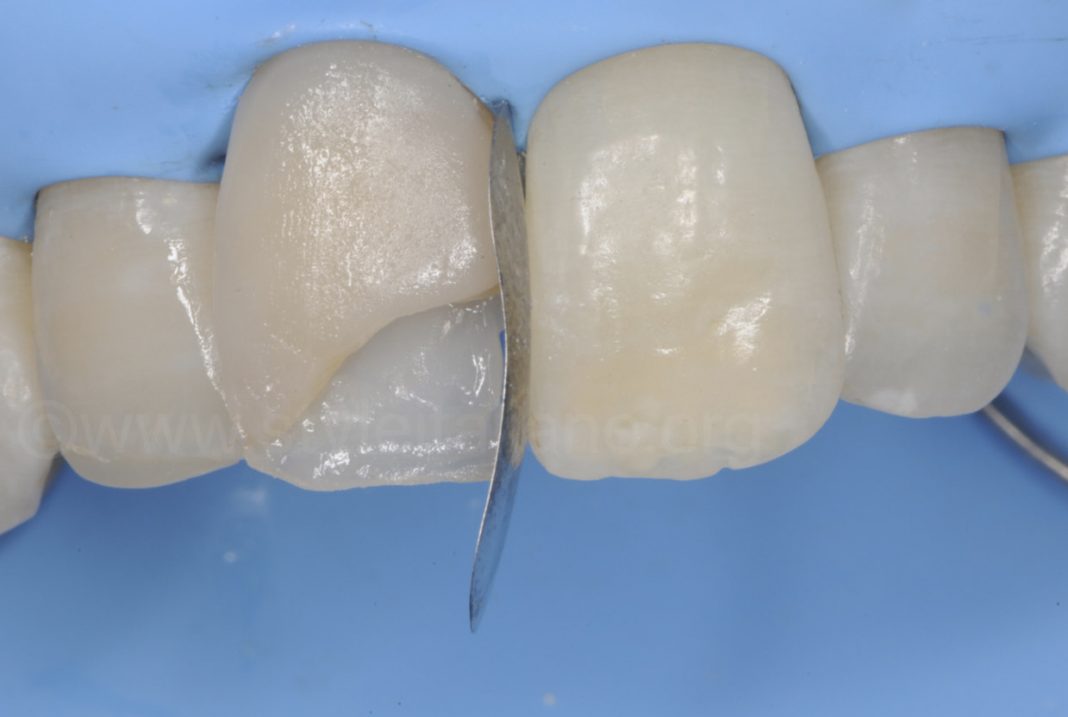

• Composite Resin: Tooth-colored, versatile, ideal for anterior and posterior restorations.

• Resin-Modified Glass Ionomer Cement (RMGIC): Combines the benefits of GIC (fluoride release and chemical bonding) with enhanced strength, wear resistance, and esthetics due to added resin. It is suitable for small to moderate restorations, cervical lesions, and as a base/liner under composites